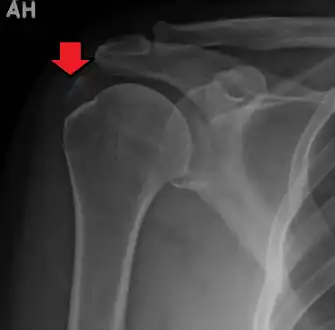

| A plain X ray of the shoulder showing calcific tendinitis | |

Calcific tendinitis is a common condition where calcium deposits form in a tendon, sometimes causing pain at the affected site. Deposits can occur in several places in the body, but are by far most common in the rotator cuff of the shoulder. Around 80% of those with deposits experience symptoms, typically chronic pain during certain shoulder movements, or sharp acute pain that worsens at night. Calcific tendinitis is typically diagnosed by physical exam and X-ray imaging. The disease often resolves completely on its own, but is typically treated with non-steroidal anti-inflammatory drugs to relieve pain, rest and physical therapy to promote healing, and in some cases various procedures to breakdown and/or remove the calcium deposits.

Calcific tendinitis is typically diagnosed by physical examination and X-ray imaging.[1] During the formative phase, X-ray images typically reveal calcium deposits with uniform density and a clear margin.[1] In the more painful resorptive phase, deposits instead appear cloudy and with unclear margins.[1] By arthroscopy, formative stage deposits appear crystalline and chalk-like, while resorptive stage deposits appear smooth resembling toothpaste.[1] Ultrasound is also used to locate and assess calcium deposits. In the formative stage, deposits are hyperechoic and arc-shaped; in the resorptive stage deposits are less echogenic and appear fragmented.[1][3]